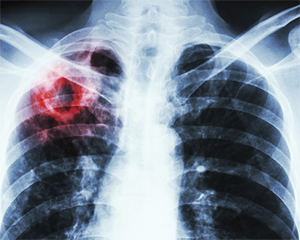

Обговорення вимог ПМГ–2022: туберкульоз

Під час другого засідання Робочої групи за напрямом лікування дорослих та дітей з туберкульозом медичні експерти фіналізували зауваження та пропозиції до двох пакетів медичних послуг Програми медичних гарантій (ПМГ) — «Супровід та лікування дорослих та дітей, хворих на туберкульоз на первинному рівні медичної допомоги» та «Лікування дорослих та дітей із туберкульозом у стаціонарних та амбулаторних умовах».